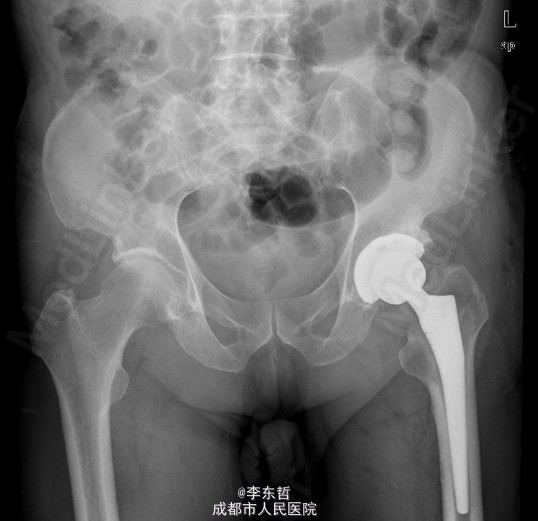

患者男,76岁,因“外伤致左髋部疼痛40多年,加重伴跛行2年”入院;患者自诉40多年前因一次摔伤致左髋关节脱位,给予手法复位后治愈,以后时有疼痛,关节活动好,不影响行走,4年前出现左髋部疼痛加重,活动后明显,休息后缓解,无腰腿痛,无肢体麻木等不适,给予对症治疗,稍有好转,以后反复发作,长时间行走后疼痛明显加重,2年前出现左下肢无力,长距离行走后出现跛行,且左髋关节有异响感;2月前出现左髋部疼痛加重,行走时尤为明显,步行约500米即出现疼痛,伴跛行,偶有静息痛;以后反复出现左髋部疼痛,并逐渐加重,严重影响日常生活;1月前于当地医院摄片提示左股骨头坏死,为求进一步治疗,遂来我院,门诊以“左髋骨关节炎”收入住院。 患者自患病以来精神、饮食、睡眠可,二便正常,体重无明显变化。

查体:左侧腹股沟中点深压痛,左髋部伴有轴向叩击痛,双下肢感觉正常,双足背动脉搏动良好。左下肢较右下肢短缩约2cm;左髋屈65°,伸0°,内收10°,外展20°,内旋5°,外旋10°,左髋活动受限,内外旋诱发疼痛;Thommas征阴性,“4”字试验阳性;左下肢肌力正常,活动良好,右侧正常 ;辅助检查:X片示:左侧股骨头塌陷、密度增高,股骨头坏死可能,左髋骨质疏松.。

初步诊断:左髋创伤性骨关节炎 诊疗计划:1、向患者及家属交待病情及注意事项。2、向上级医生汇报患者病情。3、完善血常规,心电图,肝肾功等检查,择期手术治疗。4、密切观察病情变化,根据病情及时处理。